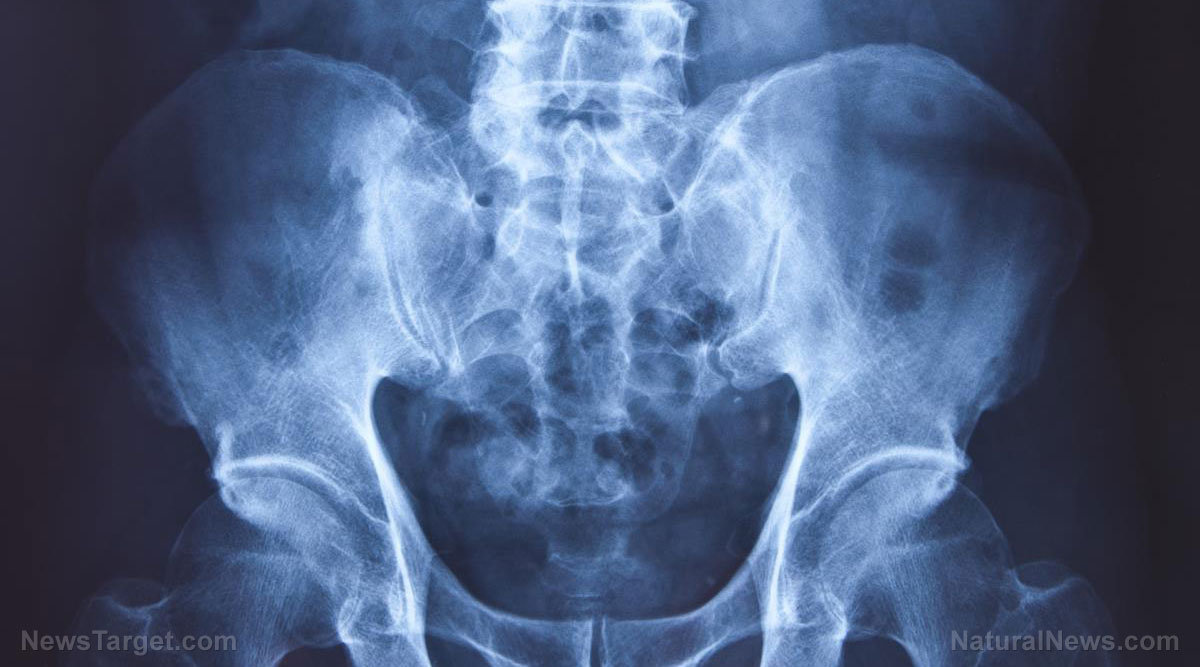

A fascinating new study published in Precision Oncology has found that a combination of three plant-based nutrients “melts away” prostate cancer cells. The study, led by University of Texas researcher Stefano Tiziani, is entitled Combinatorial treatment with natural compounds in prostate cancer inhibits prostate tumor growth and leads to key modulations of cancer cell metabolism.

“New research from The University of Texas at Austin identifies several natural compounds found in food, including turmeric, apple peels and red grapes, as key ingredients that could thwart the growth of prostate cancer, the most common cancer afflicting U.S. men and a key area of focus during Men’s Health Month, which public health advocates celebrate in June,” reports the University of Texas in Austin. “Published online this week in Precision Oncology, the new paper uses a novel analytical approach to screen numerous plant-based chemicals instead of testing a single agent as many studies do, discovering specific combinations that shrink prostate cancer tumors.”